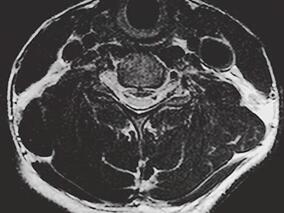

1小时条评论【病例资料】 患者,男性,34岁。因双下肢麻木无力、跛行半年,二便困难3个月于2013年2月16日入院。 现病史:患者于半年前无明显诱因出现双下肢无力,以右下肢为著,伴双膝以下发凉、麻木感,不伴有下肢肿胀、关节畸形,上述症状逐渐加重,出现右下肢行走困难,伴...